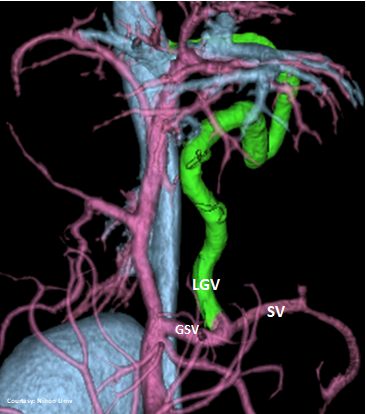

“LGC +RGV +SGV”

Left Gastro-Caval Shunt with Right Gastric Vein and Short Gastric Vein contributions

Courtesy: Nihon Univ